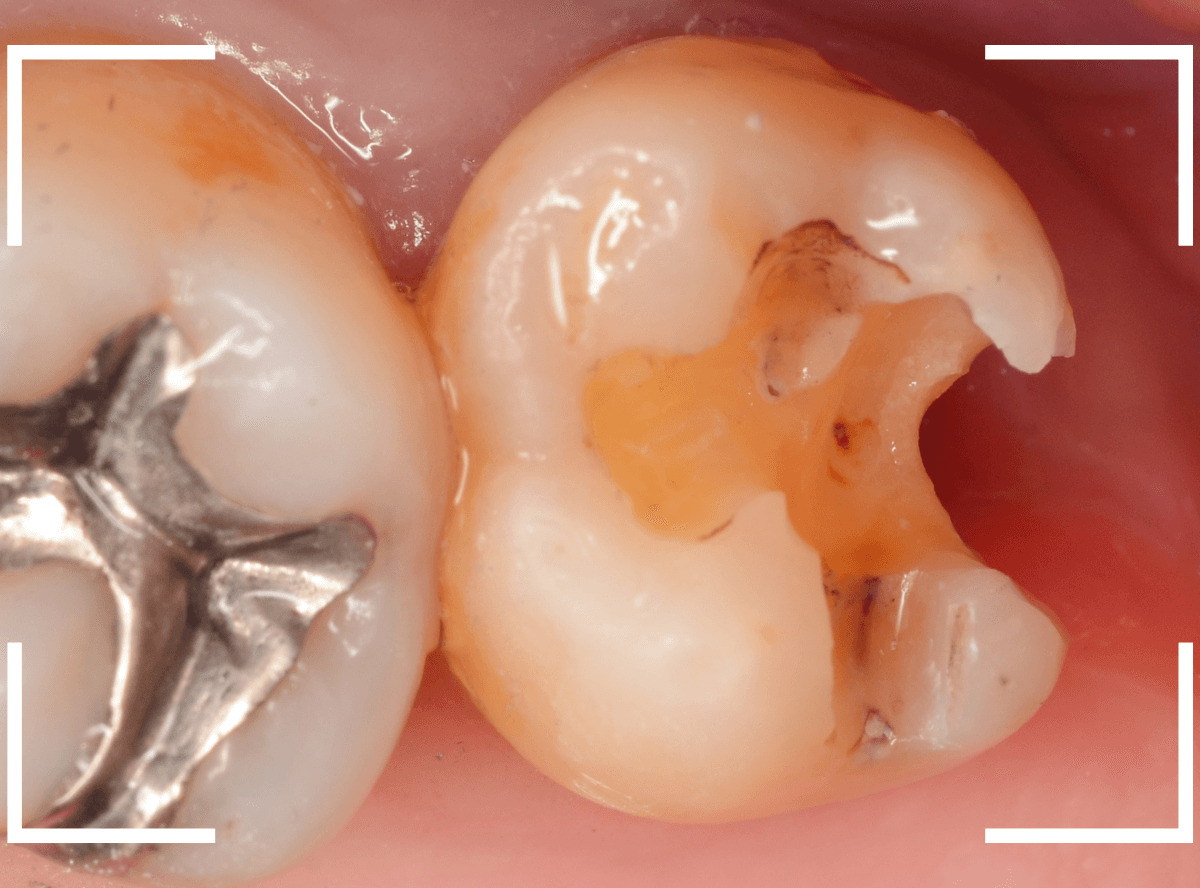

上の奥歯が痛むという訴えで来院された患者さんです。

一番奥の歯(左)が虫歯になっているのが一目でわかります。

虫歯も深そうです。

レントゲン写真で確認します。

赤い線が虫歯、青い線が歯の神経です。

歯の神経までは少し距離がありそうですが、深い虫歯であるのはわかります。

となりのつめもの(レジン)の下も虫歯になっているのがわかります。